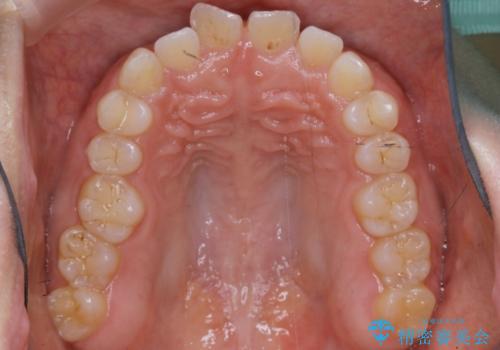

- 矯正治療を主訴にご来院されました。

すきっ歯と噛み合わせの治療をしたいとのことで、インビザラインを用いて矯正治療を行うこととなりました。

すきっ歯の場合、ガタつきを治したりするのに必要なスペースが最初から空いているため、そのスペースを利用して比較的短期間で効率よく治療を進めることが可能となります。

初診時の写真では一見噛み合わせには問題がないように見えても、実際に精密な検査を行うと改善すべき点が見つかる場合も多くあります。

当院では、矯正治療は見た目の改善が主目的ではなく機能面を改善し自然に長持ちする口腔内環境を整えることに重きを置く必要があると考えます。